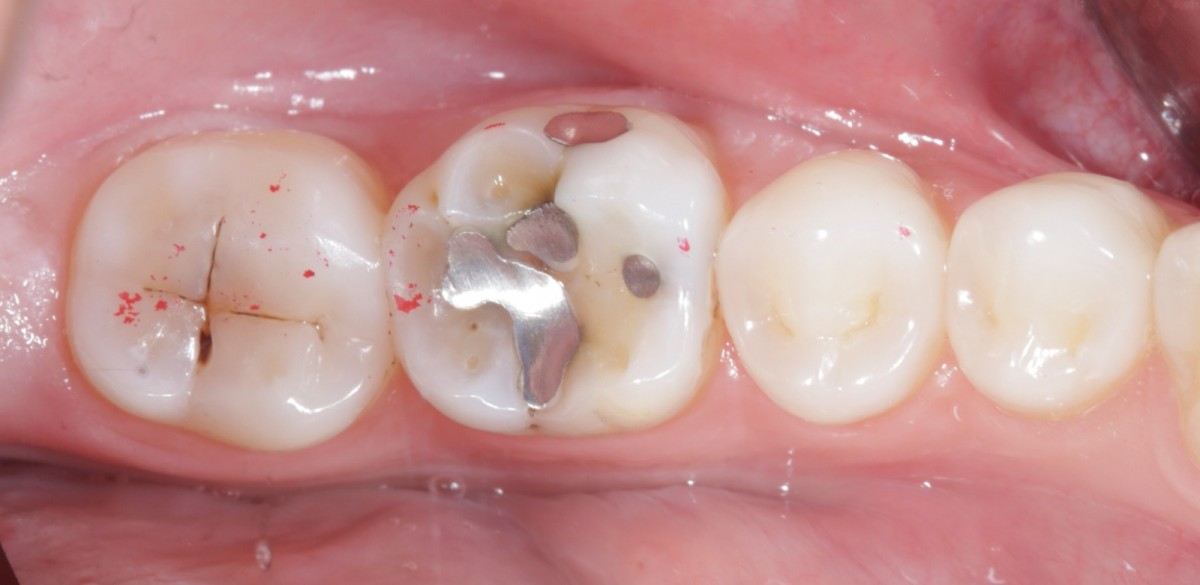

During the visit, consisting of the physical examination and instrumental examinations such as radiographs bitewings, thermal tests and compression tests (to exclude the presence of typical symptoms of a crack) at the level of the fourth quadrant, she has: amalgam restoration on dental element 4.6 associated with primary mesial caries and primary occlusal caries on 4.7.

The symptoms are not clearly identifiable by the patient but they can be traced back to dental elements 4.6 through diagnostic tests.